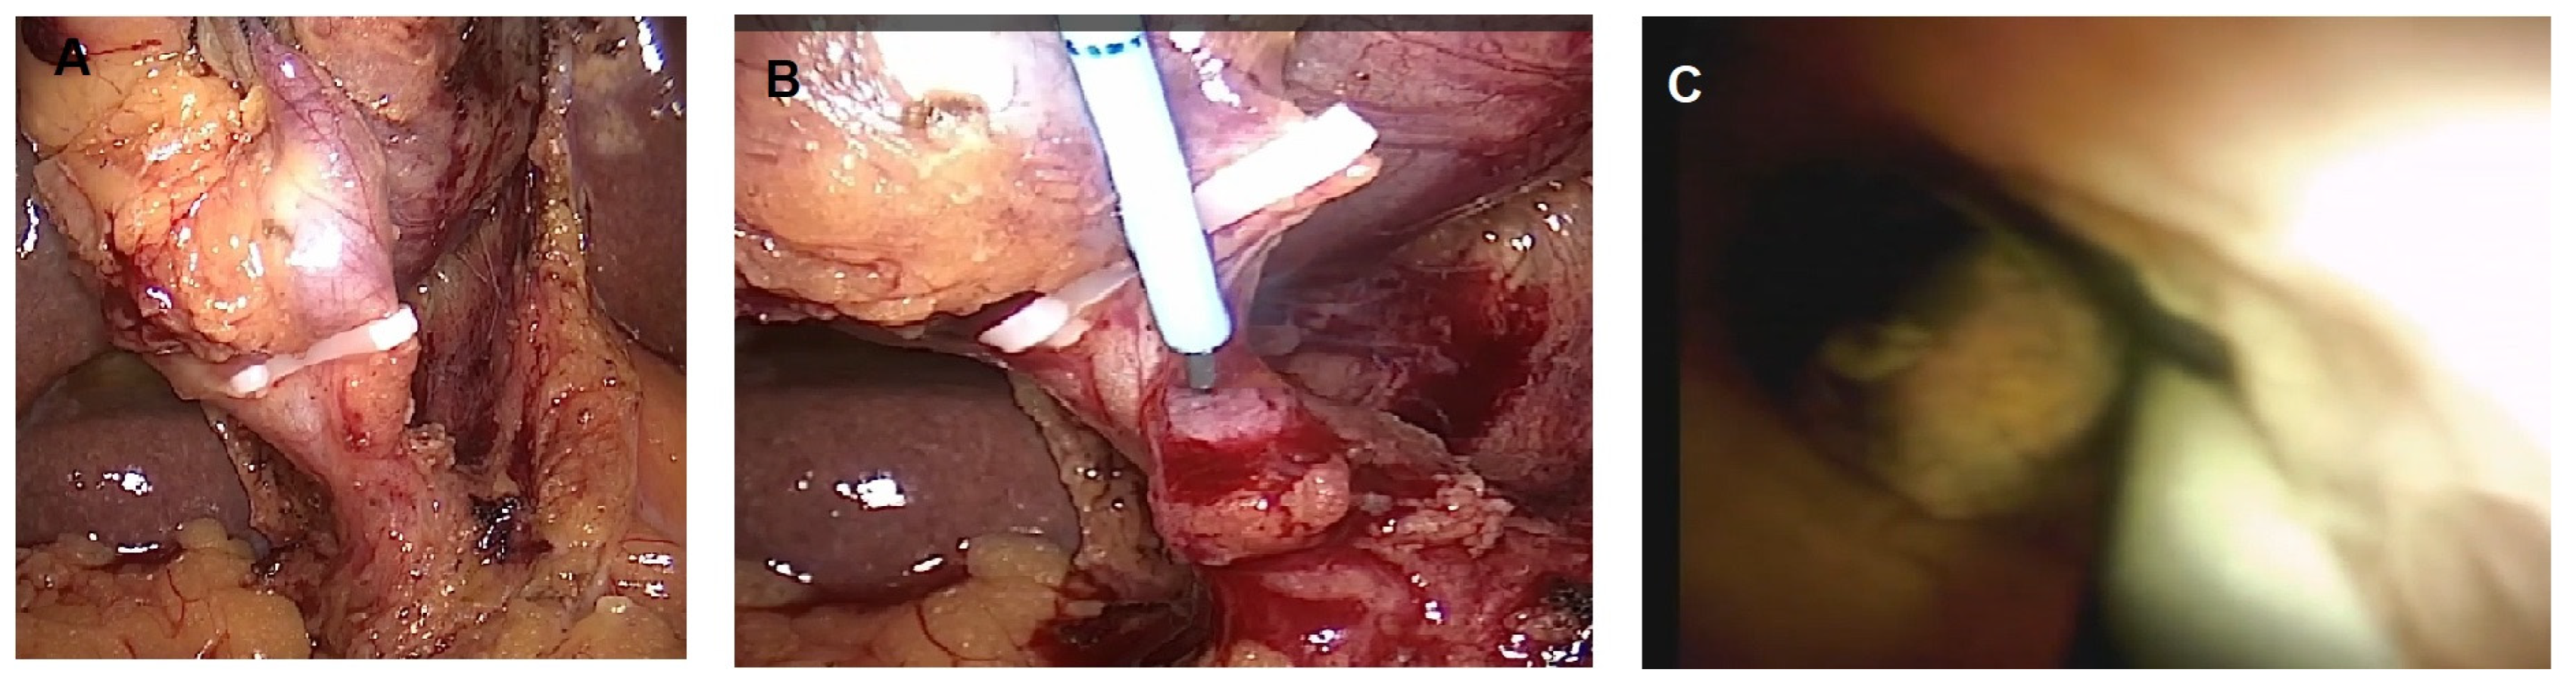

POC could also be challenging in the case of normal anatomies and successful biliary cannulation when biliary stones are located in the more proximal biliary branches, where biliary angulations may block POC passage or may create instability during therapeutic procedures. In such situations, PC may provide valid and easier access to intrahepatic/hilar bile ducts for the treatment of biliary stones [94,95,96,97,98]. In Figure 2, a case from our institution of an EHL for multiple intrahepatic lithiasis not reachable with POC for the presence of an inflammatory stricture below the stones is described.

Figure 2.

56-year-old female with intrahepatic multiple lithiasis of the sixth segment. Per-oral cholangioscopy was not feasible for the presence of an inflammatory stricture below the stones. Percutaneous cholangioscopy was performed with complete clearance of stones. (A) Multiple stones in the sixth liver segment (white arrow) above the biliary stricture (white asterisk); (B) percutaneous drainage; (C) radiological view of percutaneous cholangioscopy with electrohydraulic lithotripsy probe; (D) percutaneous cholangiography showing complete clearance of the sixth biliary segment.